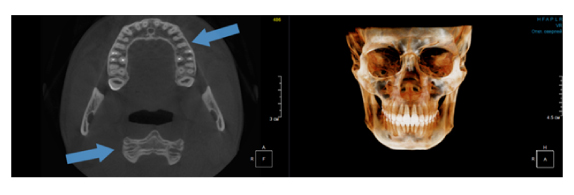

Когда мы отправляем пациента на проведение рентгенологического исследования, то подвергаем его определенному риску. Именно это нужно осознавать, так как в радиологии нет минимально безопасной дозы, поэтому любое назначение должно быть обоснованным. В связи с этим поле обзора является достаточно принципиальным параметром. Если вы врач-терапевт, занимающийся эндодонтией или ортопед, который решил оценить состояние зубов перед протезированием, то вы должны понимать, что проведение исследования с полем обзора 10x10 см будет гораздо информативнее нежели большие снимки (18x16 см и выше). В первую очередь это связано с размером вокселя, о нём я напишу чуть ниже, а второе это то, что вам придется увеличивать изображение по каждому корневому каналу, и от этого вы будете терять в качестве снимка (рис. 1). И ситуация наоборот, если вы ортодонт, то чтобы использовать весь диагностический потенциал, а также возможность загрузить данные для расчёта 3D цефалометрии, то вам нужны снимки, захватывающие весь лицевой отдел черепа. Таким образом, дентальный томограф должен обладать возможностью проведения исследований с разным FOV, обеспечивая нужды всех специалистов. Если ваша клиника базируется на терапевтическом, хирургическом и ортопедическом приёме, то на мой взгляд, можно рассмотреть дентальные томографы с полем обзора 10x10 см или 16x10 см. Последний больше актуален для тех, кто работает с ВНЧС, так как антропометрически в 16 см даже у брахицефалов сустав должен попадать.  Если в клинике есть ортодонтическое направление, функциональная стоматология, ЛОР-практика или ЧЛХ, то, безусловно, вышепредставленные снимки не будут отражать всех данных, которые необходимы для диагностики и планирования лечения. Здесь лучше рассмотреть конусно-лучевые компьютерные томографы с зоной сканирования 18x16 или 20x20 см. Особо стоит отметить понятие «сшивки». Есть дентальные томографы, которые делают один цельный снимок размерами, которые описаны выше, а есть аппараты, которым нужно провести две экспозиции и сшить изображения вместе, чтобы получился необходимый объём исследования. Как правило, вторые томографы чуть дешевле, но всё зависит от того, насколько вам нужна максимальная точность исследования. Если при сшивке челюсти и зубы, как правило, совмещаются практически идеально, то на уровне позвоночного столба происходит наслоение тканей и от него уже не избавиться (рис. 2). Второй отрицательный момент – это износ оборудования, логично, что он будет быстрее, так что экономия средств — это ещё спорный вопрос.

Рис. 1. Представлены два исследования (10x10 см и 20x20 см). На обоих изображениях хорошо видна канально-корневая система зубов, но, если масштабировать второе исследование, то качество неминуемо снизится, как и диагностическая эндодонтическая эффективность.

Рис. 2. Левый снимок представлен исследованием 20x20 см единым изображением. Стрелками показаны чёткость канально-корневой системы зуба, а также позвоночника. Правый снимок представлен исследованием 16x15 см с функцией сшивки. Стрелками обозначены чёткость зуба, но двойной контур позвоночника.